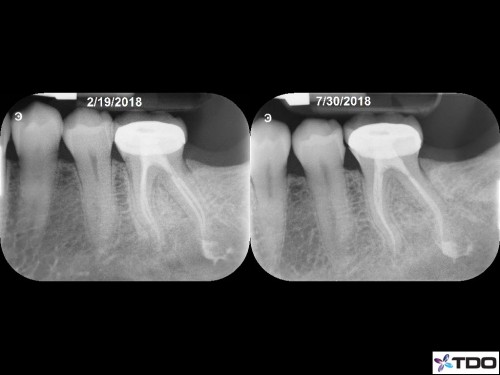

Necrotic Pulp. Symptomatic AP. 3 visits due to persistent drainage from the DL at the second visit two weeks later. Let the tooth sit in calcium hydroxide over one month before completing. Tooth was asymptomatic and dry canals at the third visit.

Asymptomatic and functional at F/U.